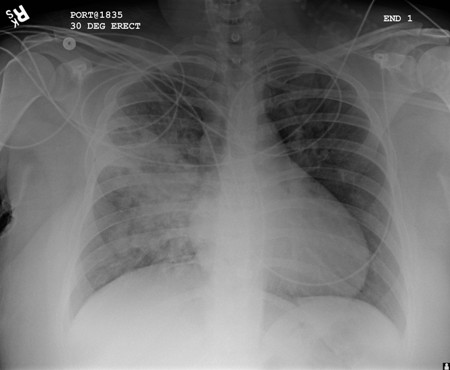

[Figure caption and citation for the preceding image starts]: Opacificações precoces mal definidas no lobo superior direito, acima da fissura menor, compatíveis com alterações precoces de pneumonia por aspiraçãoUsada com permissão de Roy Hammond, MD [Citation ends].

[Figure caption and citation for the preceding image starts]: Opacificação aumentada da região peri-hilar direita e do segmento superior dos lobos inferior e superior direitos, compatível com agravamento da pneumonia por aspiraçãoUsada com permissão de Roy Hammond, MD [Citation ends].